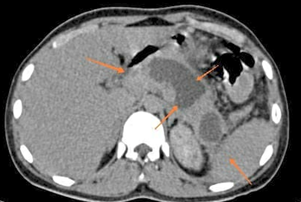

Urgent ultrasound was done which was showing paralytic ileus and bulky inflamed pancreas with ascites. Chest x ray reveals right sided pleural effusion. Contrast CT abdomen was showing decreased enhancement with evidence of acute parenchymal type of necrotising pancreatitis with intraparenchymal walled of necrosis with modified CT severity index score of 8 with ascites as shown in Figure 1. MRCP confirmed similar findings.

Figure 1 Arrow showing bulky pancreas with parenchymal pancreatic necrosis.